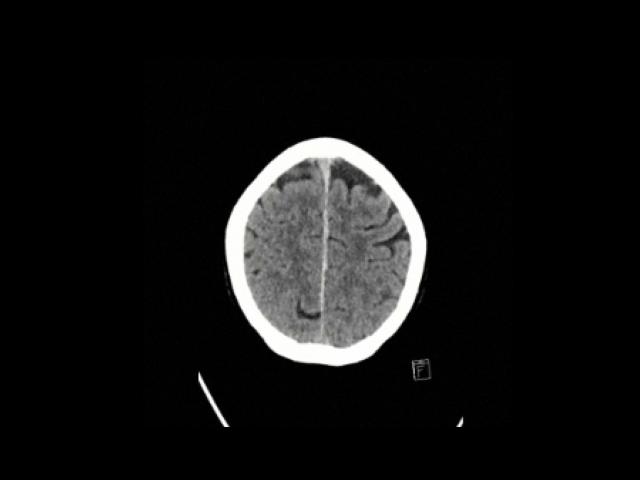

Sample Gallery